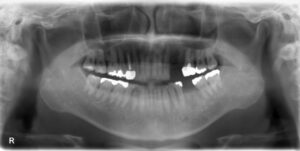

臼歯3本欠損症例

BEFORE AFTER 44歳男性/上下3本/インプラント埋込手術 【治療内容】 左上第一小臼歯、第二小臼歯、第一大臼…